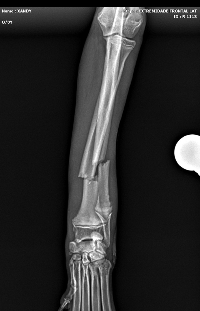

Olá, eu sou Josiane Faria, estou aqui para pedir o seu apoio em prol do Xande. Ele é um Cão de Rua, entre 6 a 8 meses, super dócil e carinhoso, que recentemente foi atropelado e sofreu fratura da pata esquerda (quebrou rádio e una), que comprometeu sua mobilidade e trouxe muita dor. Para que ele possa voltar a caminhar sem sofrimento, é fundamental realizar uma cirurgia ortopédica o quanto antes.

Os custos envolvidos no procedimento – incluindo consultas, exames de imagem, a própria cirurgia e os cuidados pós-operatórios.